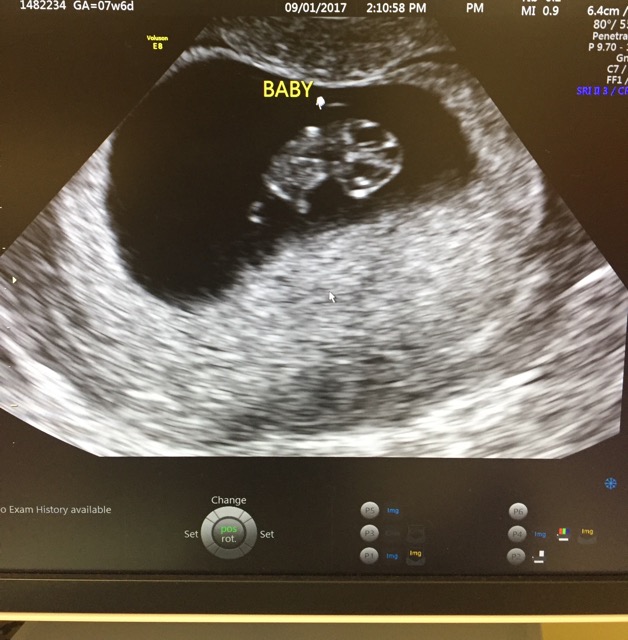

Ultrasound Leadership Academy Ultrasound in Early Pregnancy — EM Curious Internal Ultrasound Bleeding After You will be able to. A transvaginal ultrasound is an imaging procedure that allows your provider to see your pelvic cavity and the organs inside your. Some hospitals have specialist post menopausal bleeding clinics where you get the results the same day, and you can have further. There are no after effects of a transvaginal ultrasound. Specifically, this test looks. Internal Ultrasound Bleeding After.